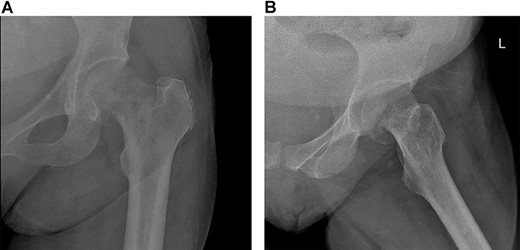

Mildly displaced fracture involving head/neck junction of the left proximal femur with suspected underlying lucency.

A 60-year-old lady, community walker with no assistance of a cane or walker, known to have PMF on ruxolitinib. She was diagnosed with PMF in a different hospital 4 months prior to presentation (Fig. 1). She presented to our clinic with 8-month history of progressive left hip pain and was not able to bear weight since the initial episode of pain without the use of analgesia. The pain was relieved with analgesics and intra-articular injections previously, which stopped showing benefits prior to presenting to our clinic. The patient did not report any history of trauma or falling down, no fever or loss of appetite. Range of motion of the hip was severely restricted due to pain. Greater trochanter tenderness was noted on examination. Initial x-rays were ordered (Fig. 2) and revealed a possible left neck of femur fracture, which prompted us to order an MRI that showed a displaced neck of femur fracture in the left hip and a non-displaced neck of femur fracture of the right hip (Fig. 3). Surgical intervention for the left neck of femur fracture was offered to the patient, while the right neck of femur fracture was asymptomatic and conservative treatment was preferred. The patient favored surgery and requested to be done as soon as possible. She was admitted from the clinic to the ward for preoperative clearance and planning.